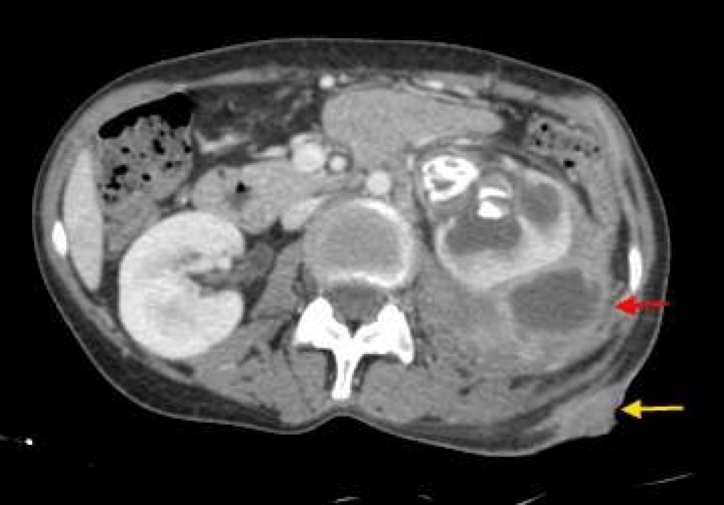

- Imaging is essential:

- CT abdomen – gold standard for diagnosis and localisation

- Ultrasound (USS) – may detect larger fluid collections